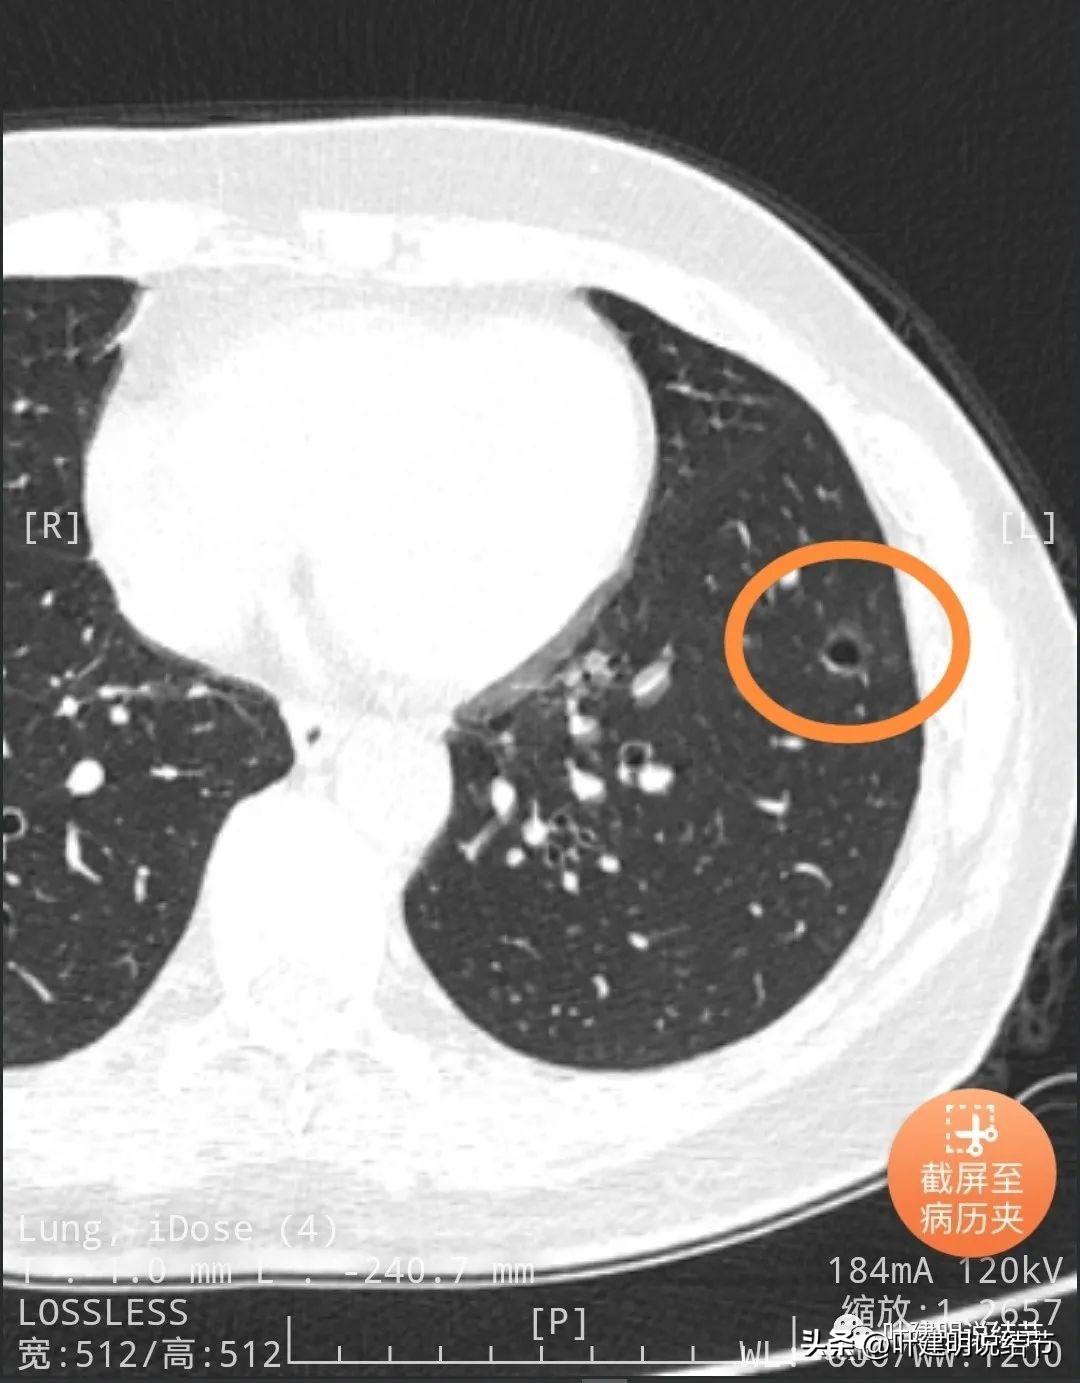

靶重建后发现病灶囊腔型,桔色箭头示进入的血管有异常增粗,而且壁显得毛糙;黄色箭头示空腔;红色箭头示整体轮廓较清;绿色箭头示有磨玻璃成分,虽然密度较低;蓝色箭头示病灶略有胸膜牵拉影响,只是力较弱而已。

上图显示了病灶轮廓与瘤肺边界其实还是清楚的。

部分边缘有毛刺征可见。

显示明显的血管征与血管异常增粗和壁毛糙。

上图显示病灶轮廓较清,有锐利细毛刺征,灶内有弯曲血管穿行。